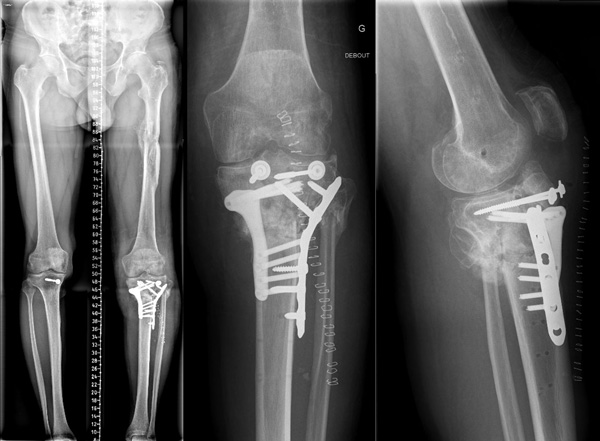

Post-operative X-Rays

1 month

• Complete extension

• Flexion 140

• Symetric varus

Post-operative X-Rays - 1 month